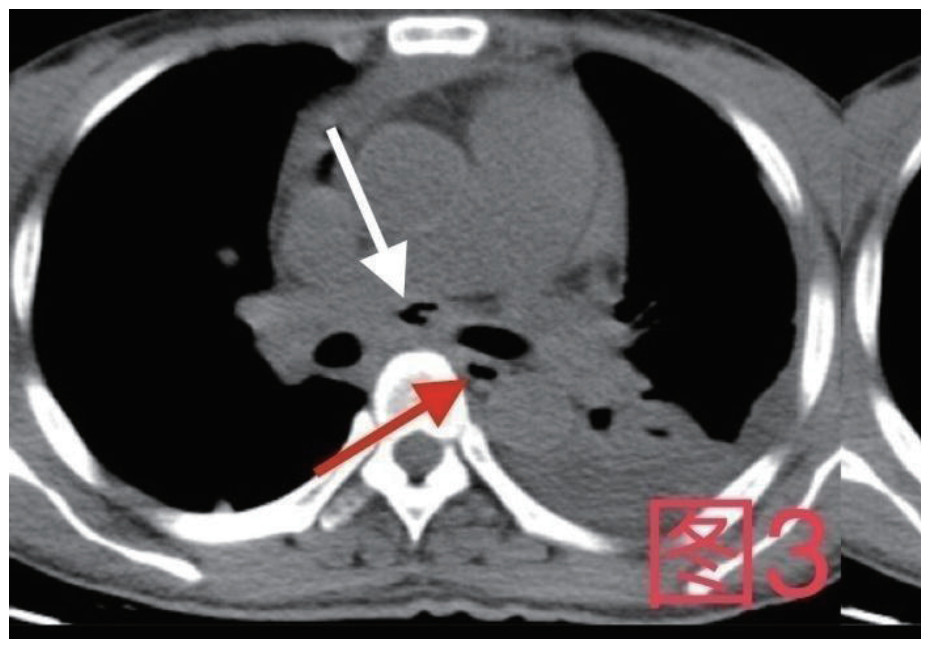

治疗经过:急诊予美罗培南0.5 g,1次/12 h抗感染,补液支持,心包引流等治疗措施,收住感染科后继续抗感染治疗,期间心包积液培养出白假丝酵母菌,加用氟康唑200 mg,1次/d, 口服,心包积液、左侧胸腔积液引流等措施,治疗10 d后复查胸部CT仍有中大量心包积液伴少许积气,纵隔积气;左侧少量胸腔积液,两肺叶间裂少许积液。对照前片(2020.10.26)心包积气及左侧胸前积液有增多,叶间裂积液新发,心包积液略有减少。右肺下叶感染,左肺下叶膨胀不全,较前右肺下叶感染有吸收,左肺下叶膨胀不全新发。考虑不能排除食管纵隔瘘,予口服碘海醇后胸部CT检查(图 3~6):约胸6椎体水平食管纵隔瘘,瘘口为相应水平食管壁右前方可能;胃镜(图 7):食道距门齿25 cm右后壁见一直径约1.0 cm凹陷,内有一小瘘口。胃镜下予钛夹2枚夹闭瘘口(图 8),同时植入空肠营养管。至此患者病情明确诊断食管心包瘘,患者经以上治疗后心包积液、胸腔积液逐渐减少,于11月13日拔除心包及胸腔引流管,因患者签字回当地就诊,予口服莫西沙星、氟康唑带药出院,出院后随访,患者未回当地医院治疗,仅在家中继续空肠营养管饲喂及口服抗菌药物治疗。

图 3 白色箭头所指为气管隆突下方纵隔内积气,红色箭头所指为食管

图 5 患者卧位第2次口服15 mL碘海醇后,白色箭头所指为纵隔内碘海醇,红色箭头为食管内碘海醇

图 6 患者俯卧位,白色箭头为纵隔内碘海醇,红色箭头为食管内碘海醇

对食管心包瘘的诊断检查需尽早进行,在急诊工作中我们可以选择口服美蓝观察心包和胸腔引流液染色情况,采取食管造影、口服碘海醇螺旋CT检查或胃镜检查。其中口服碘海醇螺旋CT检查的患者需注意可能因造影剂尚未通过瘘口导致漏诊,如本病例中患者在口服2次碘海醇后检查才出现异常结果,多次检查或改变体位进行食管造影能降低漏诊机会[10-11]。对于高度怀疑的患者进一步的胃镜检查不仅可明确诊断,也可以在诊断后给予食管支架或钛夹等治疗手段以及放置空肠营养管便于早期营养支持等支持措施[12-13]